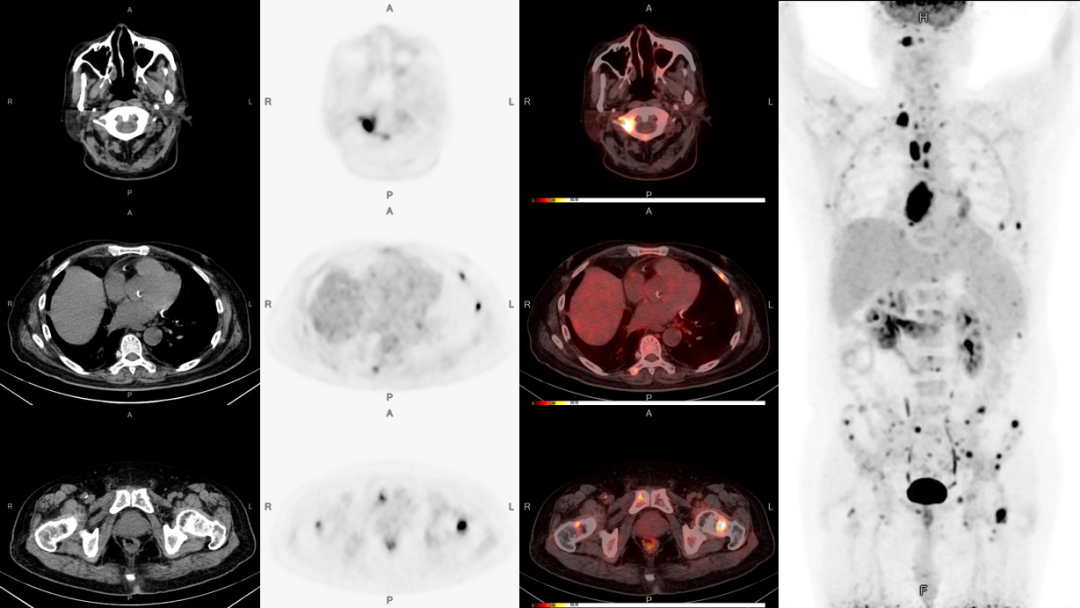

病例2:男性,51歲,反復咳嗽無痰半年余;發(fā)現(xiàn)左側(cè)鎖骨內(nèi)腫塊數(shù)月余。

3、雙股骨上段轉(zhuǎn)移可能。